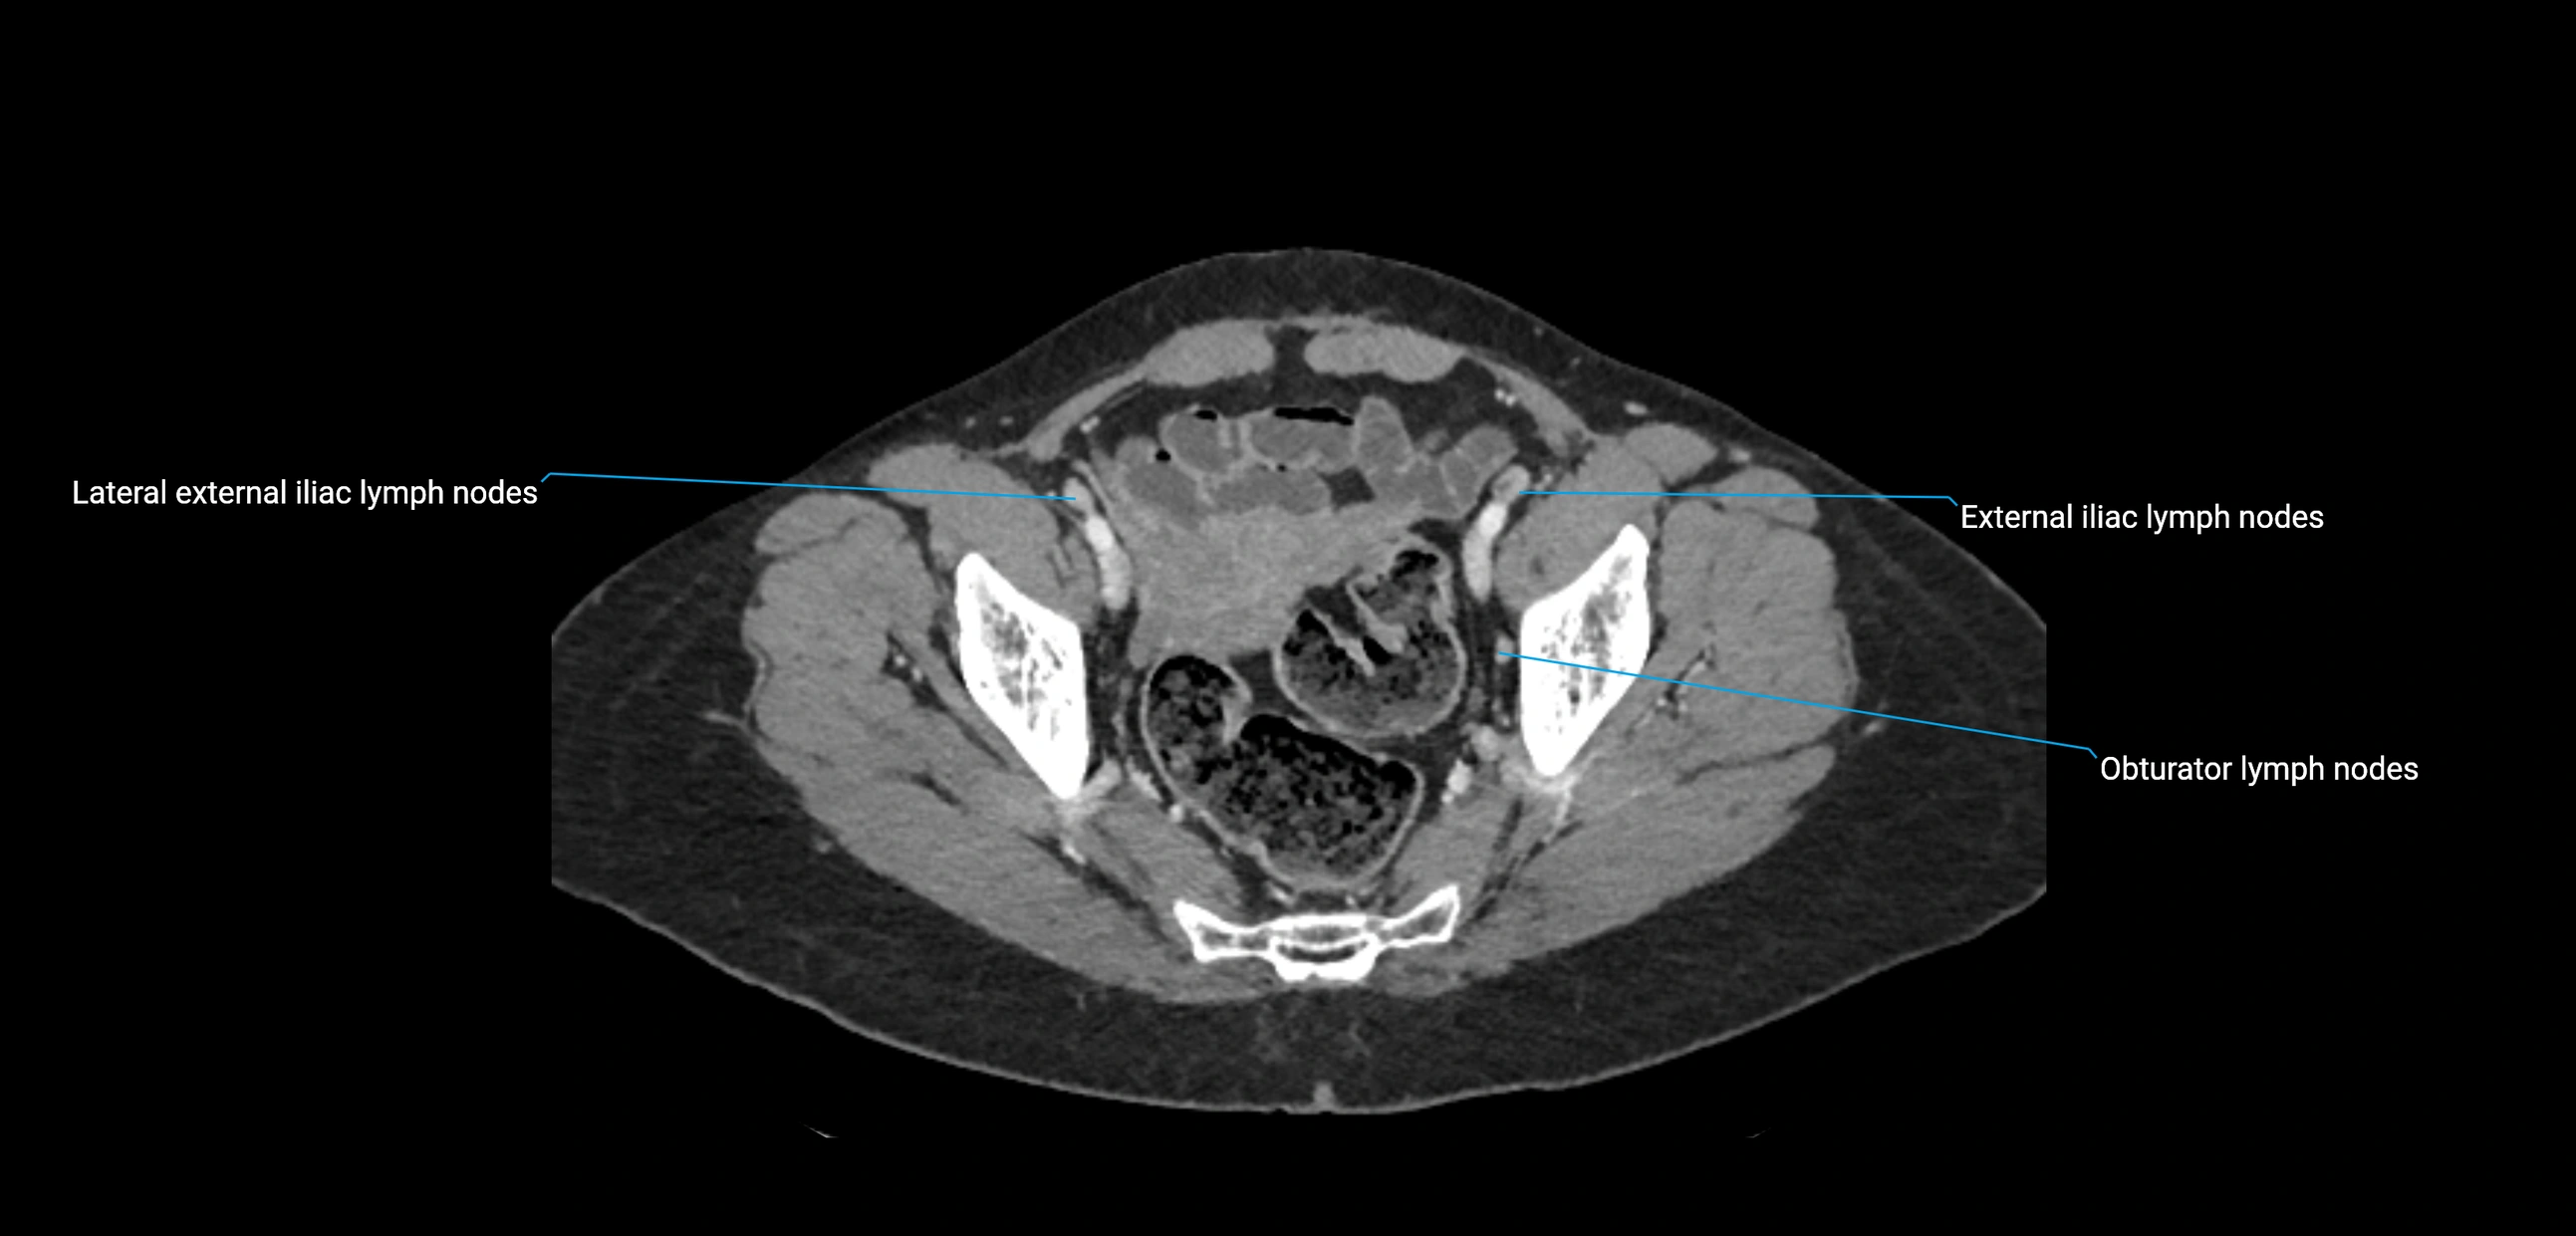

CT image

image